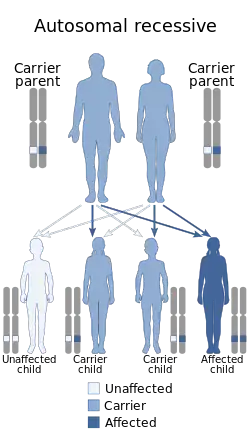

Alström syndrome (AS), also called Alström–Hallgren syndrome,[1] is a very rare autosomal recessive genetic disorder characterised by childhood obesity and multiple organ dysfunction. Symptoms include early-onset type 2 diabetes, cone-rod dystrophy resulting in blindness, sensorineural hearing loss and dilated cardiomyopathy. Endocrine disorders typically also occur, such as hypergonadotrophic hypogonadism and hypothyroidism, as well as acanthosis nigricans resulting from hyperinsulinemia. Developmental delay is seen in almost half of people with Alström syndrome.[2]

Alström syndrome is caused by a mutation in the ALMS1 gene, located on the short arm of chromosome 2 (2p13.2). The gene mutation is inherited as an autosomal recessive trait. This means both parents have to pass a defective copy of the ALMS1 gene in order for their child to have the syndrome, even though the parents may not show signs or symptoms of the condition.[10]